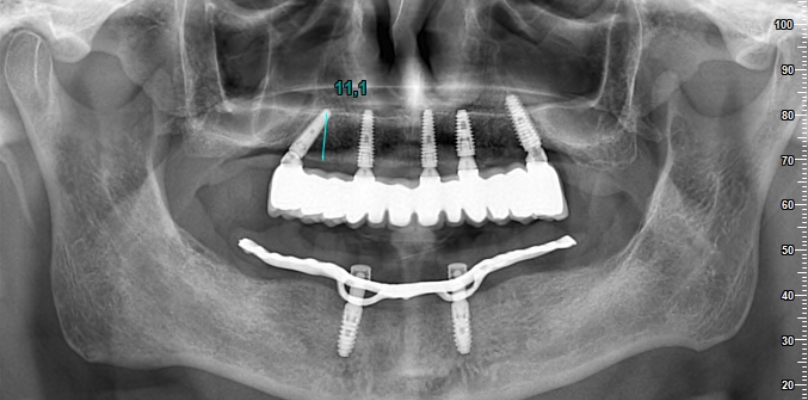

La première étape du processus de traitement consiste à prendre des images radiographiques détaillées. Ces images aident à déterminer le plan de traitement le plus approprié en évaluant la structure de votre mâchoire et votre santé dentaire. Nos radiographies révèlent à quel point le processus de traitement est extrêmement minutieux.

Dans les étapes ultérieures, vous pouvez regarder des vidéos sur la façon de placer des implants et de produire des prothèses. Ces vidéos visent à fournir une perspective informative à nos patients en montrant chaque étape du processus. Chaque étape est réalisée minutieusement par nos médecins experts.